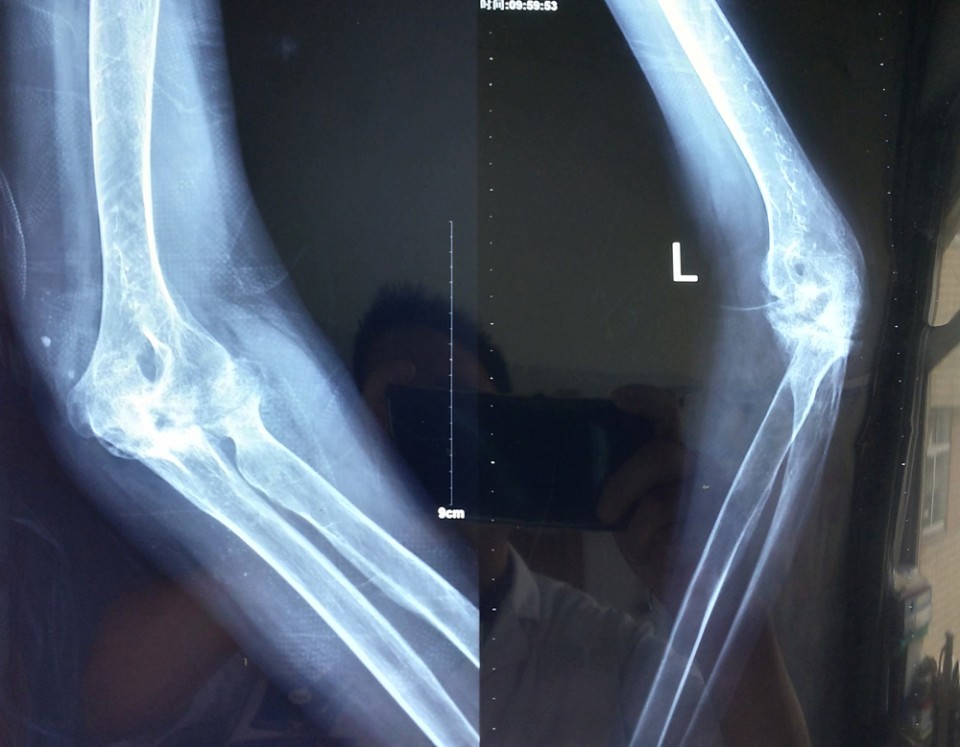

(手术前)

患者鲍女士患有类风湿关节炎20余年,双侧肘关节疼痛多年。近1年来病情加重,疼痛剧烈,双侧肘关节伸直功能和屈曲功能都严重受限,影响生活。患者于我院门诊就诊后入住关节与显微修复外科病区。